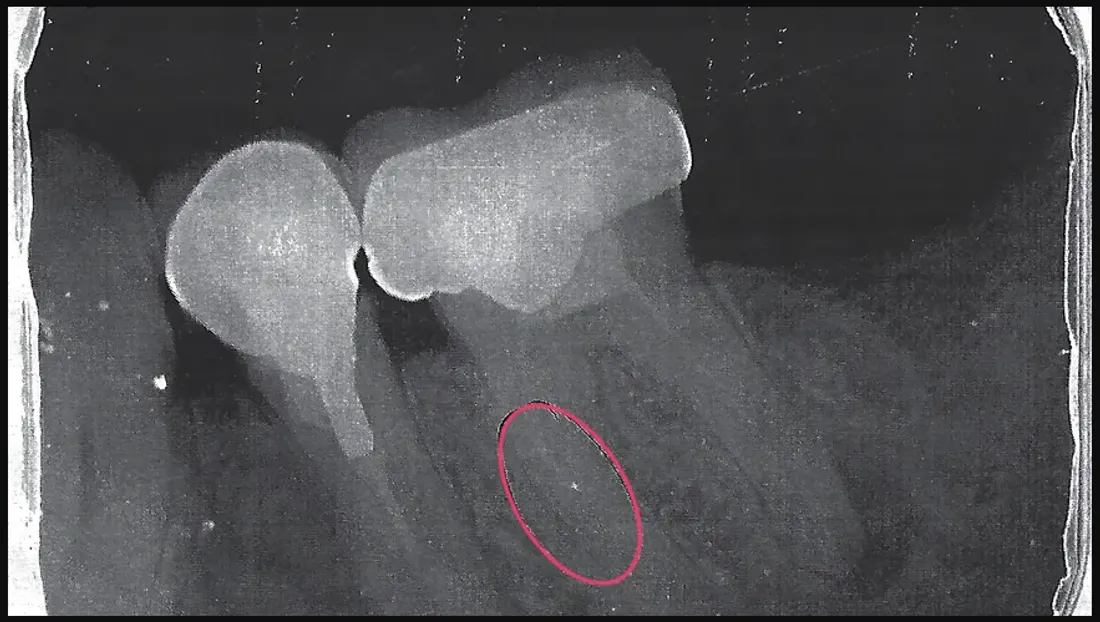

Un retraité de Saint-Julien-le-Montagnier dans le Haut-Var vient d'avoir une mauvaise surprise en allant chez son dentiste. Pascal Alexandre, 63 ans, a découvert qu'il y a 15 ans, en 2005, son dentiste de l'époque a oublié dans sa dent une aiguille utilisée pour dévitaliser sa molaire, raconte Var Matin.

Pascal s'en est rendu compte en passant une radio suite à une forte douleur aux dents. Dirigé vers un spécialiste à Aix-en-Provence, au mois d'août, Pascal va devoir subir une intervention qui coûte cher : 757 euros au total dont 550 euros pour sa poche, après participation de sa mutuelle.